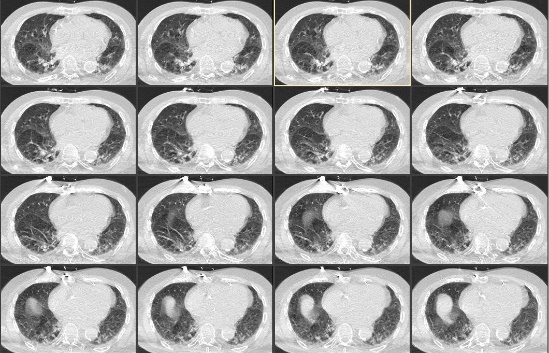

第8天复查肺部CT提示肺部感染(图 2),给予头孢他啶2.0 mg 2次/d抗感染治疗。患者第9天上午9时,患者突发心悸,气急,言语含糊。查体:体温37.3 ℃,脉搏100次/min,血压170/80 mmHg (1 mmHg=0.133 kPa),呼吸25~40次/min,指末氧饱和度SPO2 89%~95%,GCS 2-2-5分,双瞳等大等圆,光敏,双肺呼吸音减低,可闻及少量哮鸣音。血气分析:pH 7.344↓,PCO2 6.76 kPa↑,PO2 6.83 kPa↓,pro-BNP 513.3 pg/mL↑,PCT 0.09 ng/mL;血常规:WBC 9.46×109/L,NEUT% 78.5%↑;血电解质、心肌标志物、心肌酶谱、心超和心动图未见明显异常。经呼吸科和心内科会诊对症治疗后呼吸平稳,血氧饱和度维持95%以上。

| 图 2 患者第8天肺部CT |